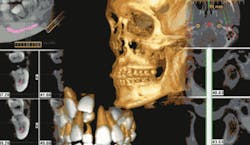

Once the scan is complete, the 3-D imaging software takes over. These 3-D images precisely replicate the positions, shapes, and measurements of every scanned facial structure, including the maxilla, mandible, TMJ, sinuses, nasal cavity, and area back to the cervical spine. Within the software, these views can be sliced and rotated for diagnostics and treatment planning. It’s like picking up a cup and looking at it from all sides instead of looking at a picture of it, and then slicing the cup any way you want to see and measure its internal structure.

Specialized procedures are particularly aided by 3-D technology. Defining the position of vital structures can help avoid complications during implant planning and placement, as well as third molar removal. For those dentists placing implants, the “nerve marking estimation tool” locates previously undetected nerve canals. The precise slices of the mandible and maxilla assist in determining implant type, size, and location.